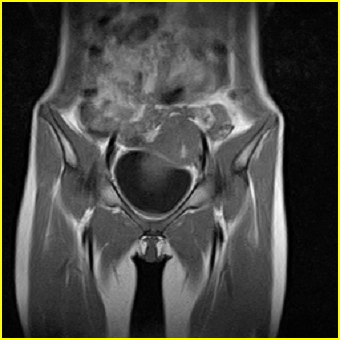

女、15岁、下腹疼痛2天,排尿困难1天。查体:处女膜闭锁,距处女膜约4至5cm处扪及一约5cm直径的圆形包块,张力较高,触痛明显、欠活动。b超提示子宫增大伴宫内增强回声团。

影像意见:子宫直肠陷凹积血。

更正影像意见:阴道积血。

处女膜闭锁,阴道积血

处女膜闭锁,阴道积血,子宫积血.

阴道积血,子宫积血.

子宫及阴道积血。

处女膜闭锁,伴子宫及阴道积血.